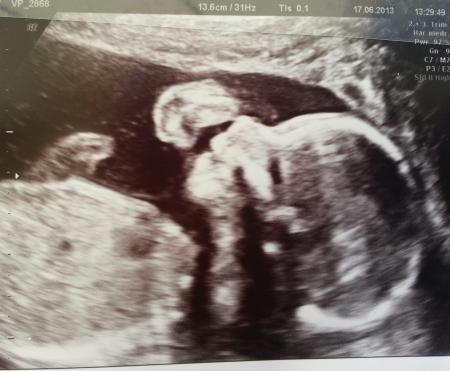

hallo Ihr lieben!!!! .....ist das schön - zurück vom Arzt und so ein tolles Gefühl " in Bauch"!!! Leider konnte mein Mann heute nicht mit, da er zu dieser Uhrzeit (11:00Uhr) natürlich arbeiten muss. Als ich im Wartezimmer ganz vertieft in meine Klatschzeitschrift war, fragte mich jemand, ob neben mir noch ein Platz frei ist.... das war mein Schatz. Hab ich mich so gefreut, er wollte mich einfach überraschen!!! Bei mir hat sie heute das II. Screening gemacht und alles super !!!!! Man konnte sehr schön das Herz und die einzelnen Kammern sehen, den Magen, beide Nieren, die Wirbelsäule, und den Bereich über der Lippe, die kleinen Füßchen usw. Fazit alles in bester Ordnung! Und dann ging die Suche nach dem Geschlecht los..... Es könnte ein Mädchen sein.....mmmmhhhhh....doch doch, also ich sag es wird ein Mädchen - so die Ärztin !!! Aber das endgültige Ergebnis sollten wir uns bei der Feindiagnostik bestätigen lassen. Wir haben süße Bilder bekommen. Die kleine Maus sieht aus, als ob man sie zum Fotoshooting eingeladen hat ( das Kinn stützt sie ganz lässig auf dem Handrücken ab - voll niedlich) Da ich auch in letzter Zeit über Unterleibsziehen klage, hat die Ärztin alles genau untersucht. MM schön fest & geschlossen. Zur Sicherheit dennoch nen Abstrich genommen. Und ich soll auch Nachmittags bzw. Abends nochmal Magnesium nehmen. Nehme es bislang nur Morgens. Wenn sich irgendetwas ändert, soll ich sofort vorbei kommen. (Foto vom Mäuschen sende ich gleich nach) Viiiiiieeeeelllll lieben Dank an Euch alle fürs Däumchen drücken Liebe Grüße sendet Euch der glücklichste Schneehase

Oh wie schön Dein Bericht liest sich ganz toll und das Bild ist super süß

So wie es da liegt und posiert ist das bestimmt ein Mädchen Richtig zucker die bilder :)

Wie es aussieht freut sich die kleine sehr. Ach Gott so ein süßes lächeln